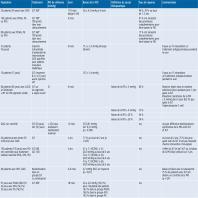

- eTableau 16-2a - Synthèse des effets indésirables au SLT signalés dans des études scientifiques

- eTableau 16-2b - Synthèse des effets indésirables au SLT signalés dans des études scientifiques

- eTableau 16-2c - Synthèse des effets indésirables au SLT signalés dans des études scientifiques